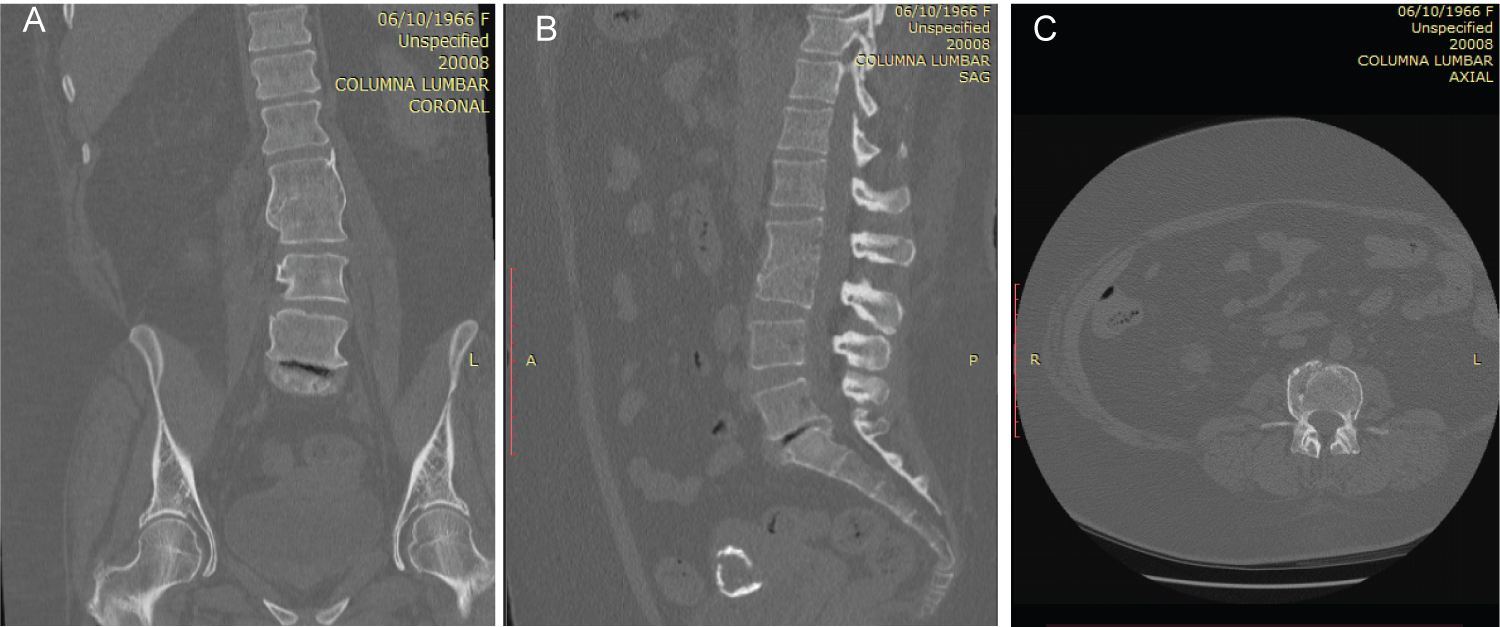

The use of tomography focuses on identifying and differentiating areas due to normal wear and tear of the joints due to age or a cause of arthropathy, as well as differentiating a possibly tumorous process (Figure 2 and Figure 3). MRI could help establish and clarify the diagnosis especially in the early stages of Charcot arthropathy of the spine [1,7,8].

Figure 2: (A,B,C) (Coronal, sagittal and axial sections respectively) in the tomography that demonstrates the complete loss of the intervertebral space at the L2-L3 level with fusion of both vertebral bodies in their entirety. View Figure 2